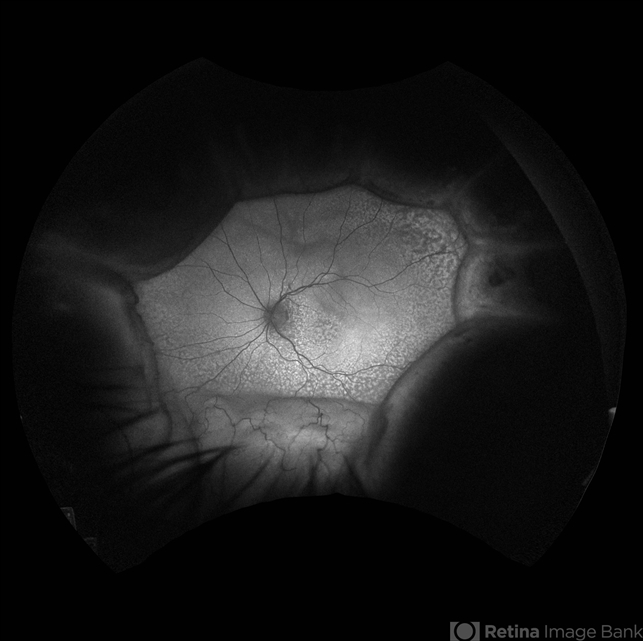

- 66 year old male presented with a 4 month vision of painless decreased vision in the left eye. Clinical findings consistent with idiopathic uveal effusion syndrome. Fundus autofluorescence imaging shows presence of leopard spotted pigmentation.